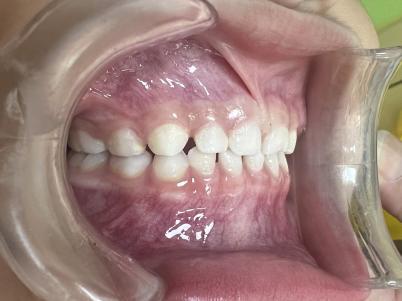

案例二:

治疗后